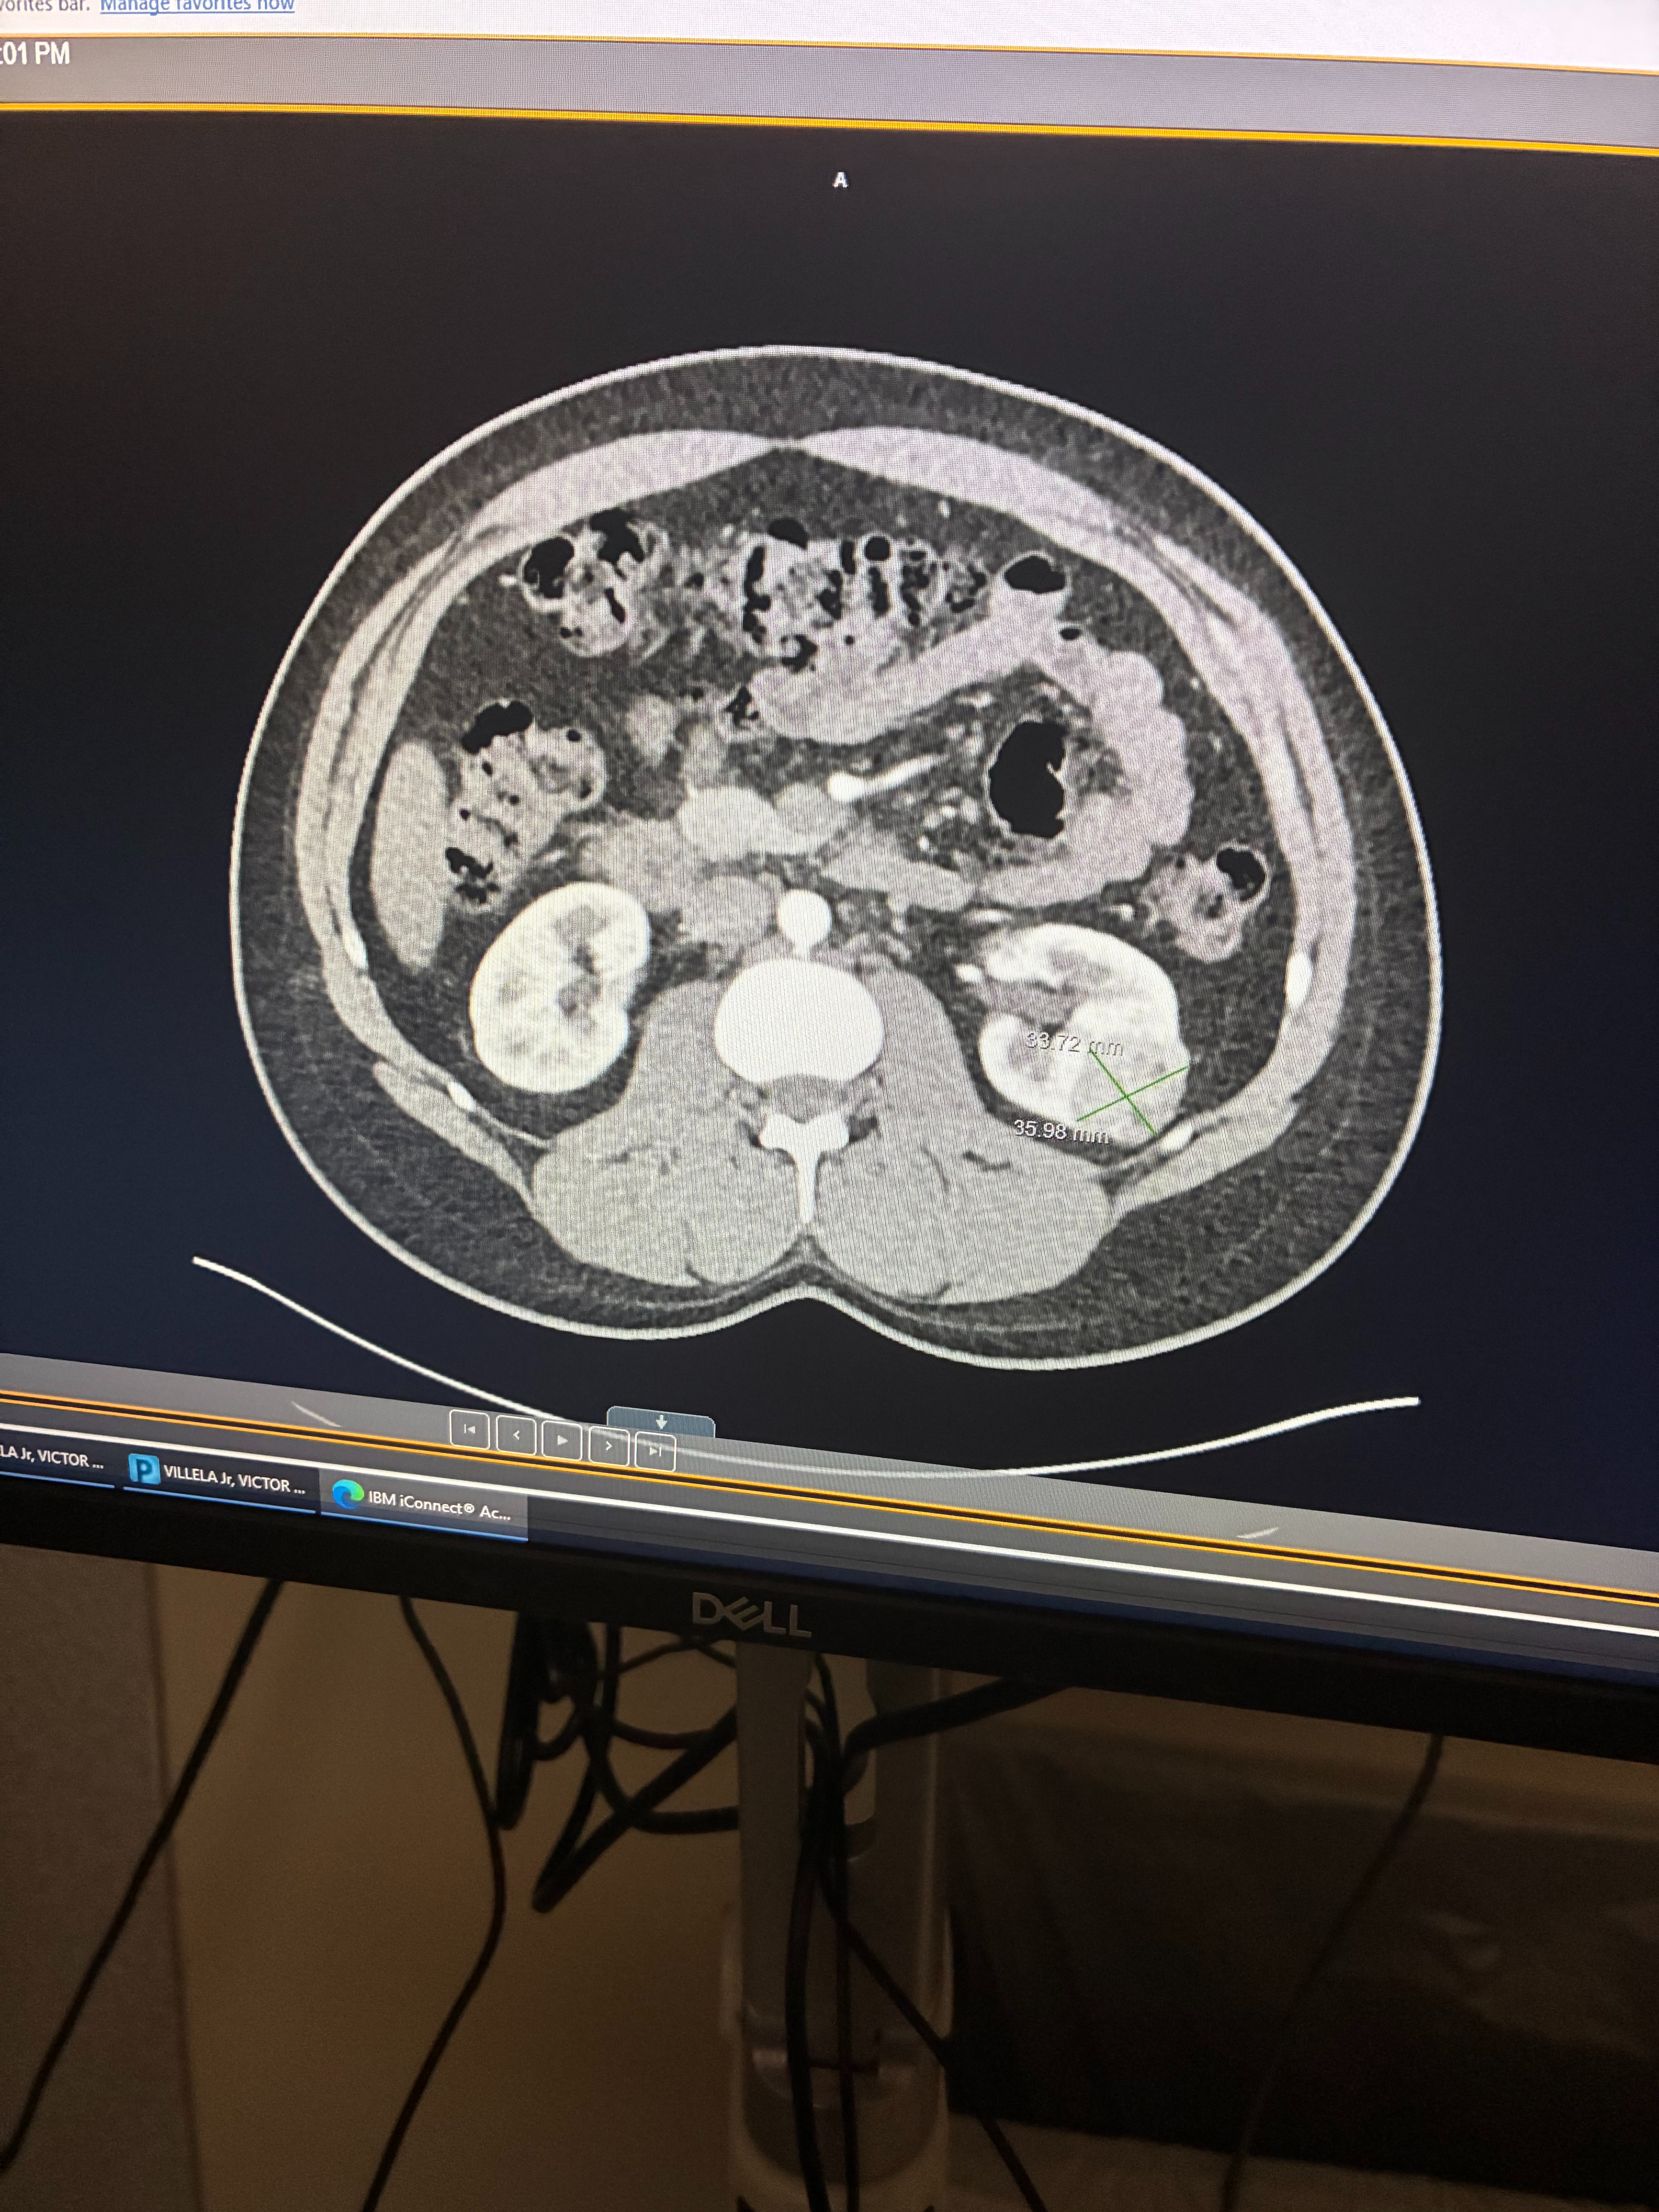

Recently, Victor suffered a fall from a second-story level while at work. During his ER visit, doctors discovered a mass in his kidney. They are 85% certain it is cancerous, and Victor is scheduled for surgery on January 20, 2026. The recovery is expected to take at least six weeks, during which he will not receive any pay. As a stay-at-home mom, I will also be recovering from a c-section after our baby arrives on February 23, 2026, and Victor will need to take unpaid paternity leave to care for our family.

Recently, Victor suffered a fall from a second-story level while at work. During his ER visit, doctors discovered a mass in his kidney. They are 85% certain it is cancerous, and Victor is scheduled for surgery on January 20, 2026. The recovery is expected to take at least six weeks, during which he will not receive any pay. As a stay-at-home mom, I will also be recovering from a c-section after our baby arrives on February 23, 2026, and Victor will need to take unpaid paternity leave to care for our family.